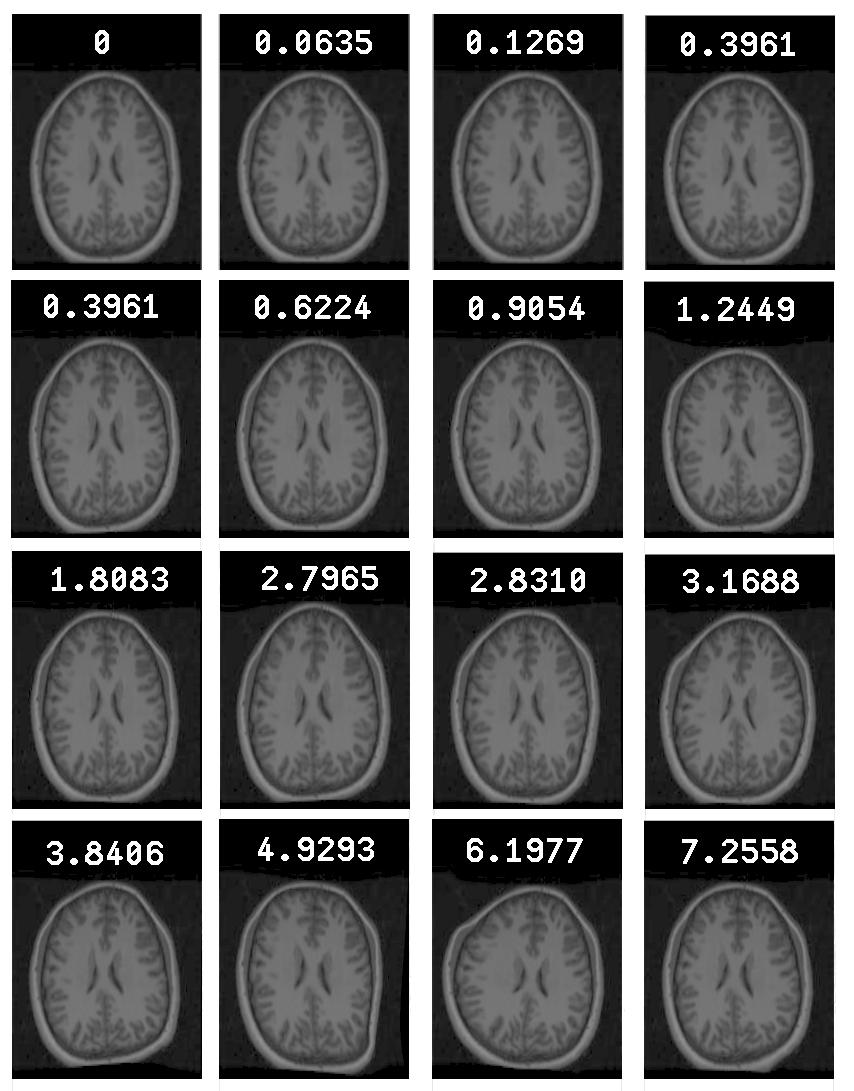

In order to perform a systematic evaluation of the effects of misregistration, multiple image sets were created, based on the MGH Dataset, but with controlled degrees of misregistration. To create a misregistered set, the original image set was taken and had applied to it a set of smooth pseudo-random spatial warps, based on biharmonic Clamped Plate Splines []. The warp for each image was controlled by 25 randomly placed knot-points, each displaced in a random direction by a distance drawn from the positive half of a zero mean Gaussian with SD ${\sigma}$, which controls the degree of misregistration. This provided a very general family of warps. The degree of misregistration was quantified by measuring $d$, the magnitude of pixel displacement averaged over the whole image. A total of 70 misregistered image sets were generated - 10 warp-set instantiations for each of 7 different values of $d$ (0.0643, 0.249, 0.685, 1.36, 2.21, 2.76, and 4.15 pixels). Examples of warped images are shown in Figure [*].

Figure: An original image from the MGH Dataset (top left) and examples of warped versions of the same image obtained using different values of $d$, the mean pixel displacement (shown on each image).

Image example_warp_mangnitude_brains_16

Although this is not an ideal way to ensure that introduced distortion mimics what one would find in real brains, such distortions are identical to those which are applied in order to solve the registration problem (just working in reverse) and all the warped brains look like possible actual brains.

The scales of deformation were carefully chosen such that they provided more insight into the behaviour of the experiments at points near the correct solutions. The deformations at the lower end of the scale were greater in terms of number and sample points in the graphs likewise. The greatest level of deformation was not exceeded in these experiments because greater deformation did not seem to result in brain images whose appearance looked quite so reasonable. A deformation too great would explore situations that are less likely to be encountered in practical applications.